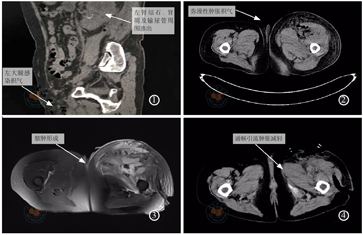

临床资料患者,女性,66岁,因"反复左腰部疼痛伴发热2个月,加重伴左下肢肿胀2 d"于2018年3月27日入院。查体:持续高热,体温最高达39℃,心率110次/min,血压83/55 mmHg,左腰部触及一囊性包块,边界清楚,有波动感,大小9.0 cm×8.0 cm,左肾区叩痛,左侧腹股沟区、左侧大腿肿胀明显,伴压痛,左侧大腿上段近腹股沟区可触及皮下积气,左小腿压痛,轻度红肿,足背无明显肿胀,足背动脉可扪及,末梢循环可。辅助检查:血常规:白细胞15.72×109/L↑,中性粒细胞绝对数14.86×109/L↑;生化:C反应蛋白266.57 mg/L↑,降钙素原4.82 ng/ml↑,白介素6 344.60 pg/ml↑,尿素氮13.40 mmol/L↑,肌酐185.4 μmol/L↑,白蛋白22.1 g/L↓。下腹盆腔CT:左输尿管上段结石,左肾盂肾盏结石,左肾感染,左肾周脓肿,左侧结肠旁沟、左侧髂腰肌、左大腿根部感染伴积气(图1)。左大腿CT平扫:左侧膝关节及大腿、腹股沟区、髋关节周边皮下组织、肌间隙肿胀并弥漫积气,考虑蜂窝组织炎(图2)。入院诊断:感染性休克并全身多器官功能不全,左侧肾周脓肿,左肾输尿管结石并左肾积水,左侧膝关节及大腿、腹股沟区、髋关节周边皮下组织蜂窝织炎。全麻下多学科联合"行经尿道右侧双J管引流术+左肾切除术+左侧肾周脓肿清创引流术+降结肠修补、肠粘连松解术+左下肢切开清创引流术",术中见肾脏中极坏死破裂,肾周筋膜、腹膜后、肾周、腰大肌大量脓性坏死物质,约1 000 ml,与腹膜降结肠黏连较重,请胃肠外科行结肠浆膜修补。术中留取脓性坏死物送培养。术后转ICU予敏感抗生素抗感染、负压封闭引流、输血、补液等对症支持治疗,患者左大腿肿胀较前缓解,皮温较前降低,病情平稳后转回专科治疗。术后第2天患者突发高热伴左大腿皮温升高、肿胀加重,并逐渐形成多发脓肿伴波动感,行左大腿MRI提示:左大腿脓肿,大腿根部后外侧切开引流术后,左大腿全部软组织显著肿胀,左大腿前、内侧肌群部分肌间及皮下积液、积气,考虑弥漫性感染并脓肿形成(图3)。术后第6天左大腿脓肿破溃,见脓性分泌物流出,予行左侧大腿脓肿切开引流术+取出术,留取大腿脓性分泌物送培养。肾脓肿和大腿脓肿分泌物细菌培养均阴性。术后患者感染指标下降,无发热等感染症状,左大腿肿胀减轻(图4),皮温正常,对症治疗2周后出院。